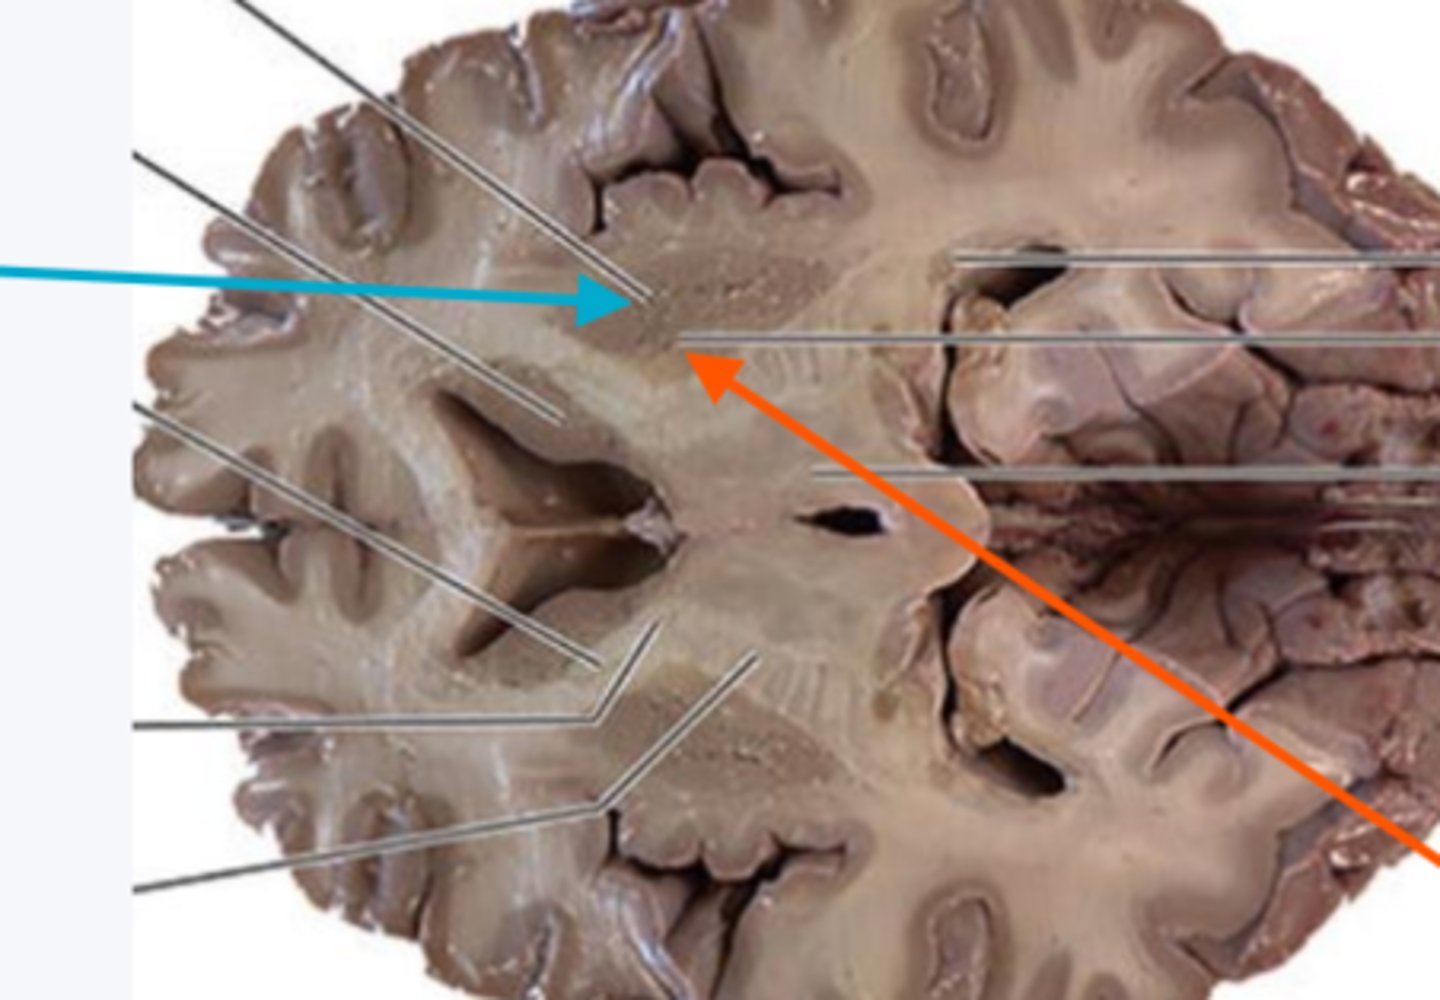

what is the blue arrow pointing to?

blue arrow is pointing to which structure?

The area the blue arrow is pointing to?

structure blue arrows are pointing to?

What area is the blue arrow pointing to?